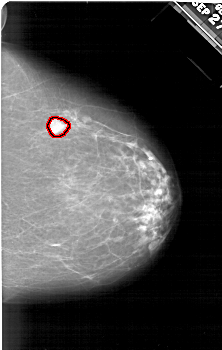

A_1895_1.RIGHT_CC

RIGHT_CC LINES 6286 PIXELS_PER_LINE 3991 BITS_PER_PIXEL 12 RESOLUTION 43.5 OVERLAY

FILE: A_1895_1.RIGHT_CC.OVERLAY

TOTAL_ABNORMALITIES 1

ABNORMALITY 1

LESION_TYPE MASS SHAPE IRREGULAR MARGINS ILL_DEFINED

ASSESSMENT 5

SUBTLETY 5

PATHOLOGY MALIGNANT

TOTAL_OUTLINES 1

BOUNDARY